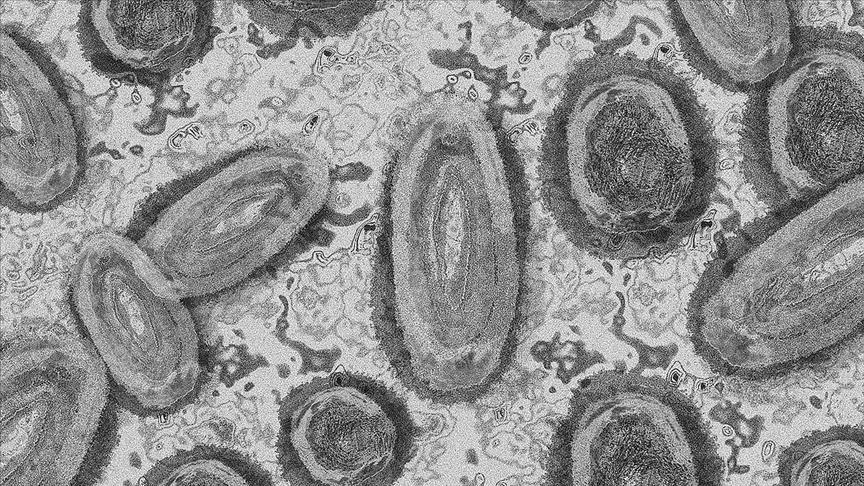

Uganda's mpox caseload rises to double-digit, health official says

The number of patients in Uganda infected with a new variant of the mpox virus has risen to 11, with a senior health official reporting that no deaths have occurred across the country as of Saturday.

Henry Gatyanga Mwebesa, director general of the Health Services of the Ministry of Health, told reporters in Kampala that all of the patients are infected with the clade 1b strain of the virus, which is believed to be a deadlier variant that can spread through skin-to-skin contact.

The World Health Organization (WHO) declared mpox, formerly known as monkeypox, as a public health emergency of international concern on August 14, after the new variant that appears to spread more easily between people, was identified, emphasizing that mpox is “not the new COVID.”

Mpox infections cause flu-like symptoms and pus-filled lesions, and they spread through close physical contact. It can also be spread by touching virus-infected objects like bedding, clothing, and towels.